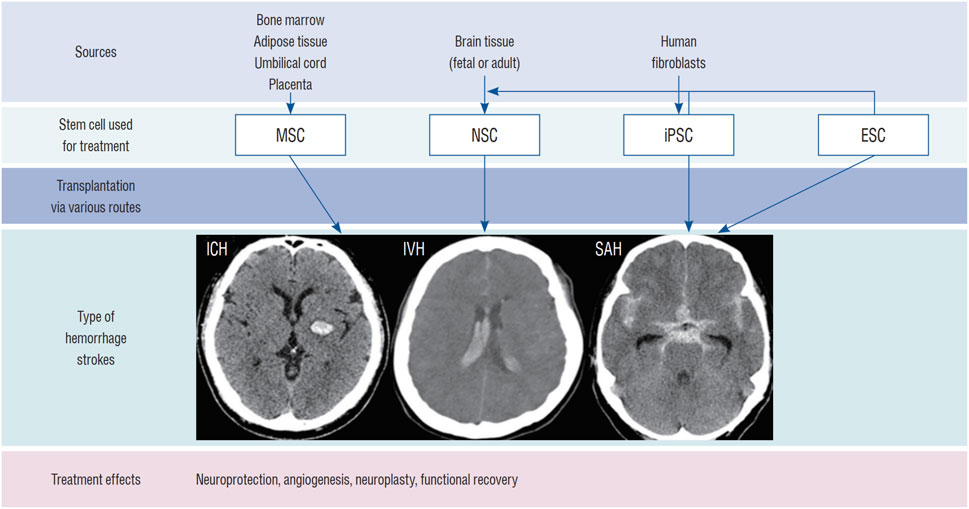

其次,多能干細胞分化是另一重要外源性途徑,主要包括胚胎干細胞和誘導(dǎo)多能干細胞。胚胎干細胞雖能分化為神經(jīng)干細胞,但存在倫理爭議、免疫排斥和致瘤風(fēng)險;而誘導(dǎo)多能干細胞通過體細胞重編程獲得,避免了倫理問題,但制備過程耗時且存在類似的安全隱患,制約了其臨床轉(zhuǎn)化。

最后,體細胞重編程和轉(zhuǎn)分化技術(shù)提供了更直接的生成方式,例如利用病毒載體或轉(zhuǎn)錄因子將成纖維細胞等體細胞轉(zhuǎn)化為神經(jīng)干細胞或神經(jīng)元。盡管轉(zhuǎn)分化方法相對簡便,但病毒載體可能帶來致瘤風(fēng)險,且轉(zhuǎn)化過程可能產(chǎn)生不必要的副產(chǎn)物,仍需進一步優(yōu)化以提高安全性與效率。

目前,神經(jīng)干細胞移植主要通過腦內(nèi)移植、鞘內(nèi)/腦室內(nèi)注射(經(jīng)腦脊液途徑)、血管內(nèi)注射和鼻內(nèi)給藥等途徑進行。最常用的方法是直接腦內(nèi)移植。然而,每種方法都有其獨特的優(yōu)缺點,目前尚未確定統(tǒng)一的移植途徑(圖1)。

包括鼻內(nèi)給藥,該方法利用嗅神經(jīng)通路,可無創(chuàng)地將細胞遞送至腦內(nèi),最大限度地減少繼發(fā)性損傷。例如,Sun等人在動物模型中發(fā)現(xiàn),鼻內(nèi)給予缺氧預(yù)處理的間充質(zhì)干細胞后,能在腦出血腦組織中檢測到這些細胞。此外,腹腔注射以及結(jié)合生物材料或納米技術(shù)的聯(lián)合給藥途徑,也在探索中,旨在進一步提高移植細胞的存活、滯留和靶向效率(圖1)。

總體而言,胚胎干細胞和誘導(dǎo)多能干細胞雖分化潛能強,但分別面臨倫理、免疫原性和致瘤性挑戰(zhàn);神經(jīng)干細胞修復(fù)功能明確但獲取困難;間充質(zhì)干細胞則因易得性和良好的安全性被廣泛研究。

推進腦出血的干細胞治療需要整合生物材料、基因工程和預(yù)處理策略以提升療效。盡管前景看好,但目前仍缺乏大規(guī)模、設(shè)計嚴謹?shù)哪X出血臨床試驗和長期安全數(shù)據(jù)(圖3)。未來研究需著重優(yōu)化給藥途徑、劑量、時機以及符合藥品生產(chǎn)質(zhì)量管理規(guī)范的大規(guī)模細胞制備工藝。